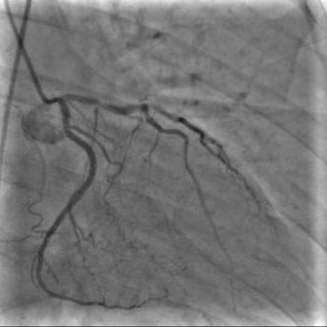

X-ray angiography is the most used imaging modality to visualise blood vessels for interventional purposes such as stenting of stenosed vessels or for diagnostic purposes such as assessment of myocardial perfusion or stenosis grading. To minimise ionising radiation exposure of the patient and medical personnel during image acquisition, low power X-Rays are used resulting in noisy and low contrast images. In the context of diagnosis, the main object of interest is the vascular tree, its branchings and variations in thickness. It is therefore necessary to accurately highlight the vessels in consecutive frames to reduce the noise and improve contrast. In addition, in interventional procedures, identifying interventional instruments (catheter, wires) is also needed in order to better plan and control their positioning. Efficiently discriminating between instruments and vessels as well as other anatomical structures that may have similar appearance is crucial during the interventions. Figure 1(a-c) shows an example of an angiogram sequence. Note large non-rigid motion between frames as well as the ambiguity between vessels and the catheter. Figure 1(e) shows a frame from a different sequence of the same patient but taken at different scan and angle and (f) shows a different patient. There is a significant difference in vessel as well as catheter locations in all three sequences, which we consider as independent examples. Figure 1(d) shows the ground truth segmentation of the first frame.

The dataset consists of anonymised fluoroscopy X-Rays of 26 different patients. The images were acquired during stent placement using a General Electric Innova 2000 system and stored according to standard medical protocol in DICOM format. In total the dataset includes 36000 frames corresponding to 365 distinct video sequences with an average of 98 frames each. Different sequences of the same patient were taken at different angles and stages of the procedure therefore they differ significantly as shown in Figure 1(c)(e)(f). Each frame is rescaled from to due to memory constraints.